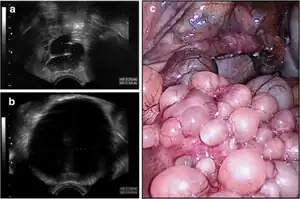

| Transvaginal ultrasound showed cystic formations in the areas of the right fallopian tube (a) and fundus uteri (b), (c); uterus (front) with right tube and right abdominal wall (background). | |

Endosalpingiosis is a condition in which fallopian tube-like epithelium is found outside the fallopian tube.[1] It tends to occur in females after menopause, and may be found on ovaries, uterus, peritoneum, bladder, or in retroperitoneal lymph nodes.[1]

It is characterized by cysts with tubal-type epithelium (e.g. ciliated epithelium) surrounded by a fibrous stroma. It is not often associated with hemorrhage.